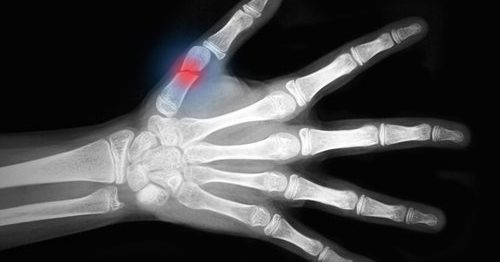

Como acelerar a cicatrização de uma fratura óssea

Uma fratura óssea, tanto completa quanto parcial, é um grande trauma para o corpo. Felizmente o nosso organismo tem a capacidade de regenerar o tecido ósseo, mas às vezes este é um processo lento.

Apresentamos alguns alimentos e remédios que ajudarão a aumentar o número de novas células e vasos sanguíneos que reconstruirão o osso.